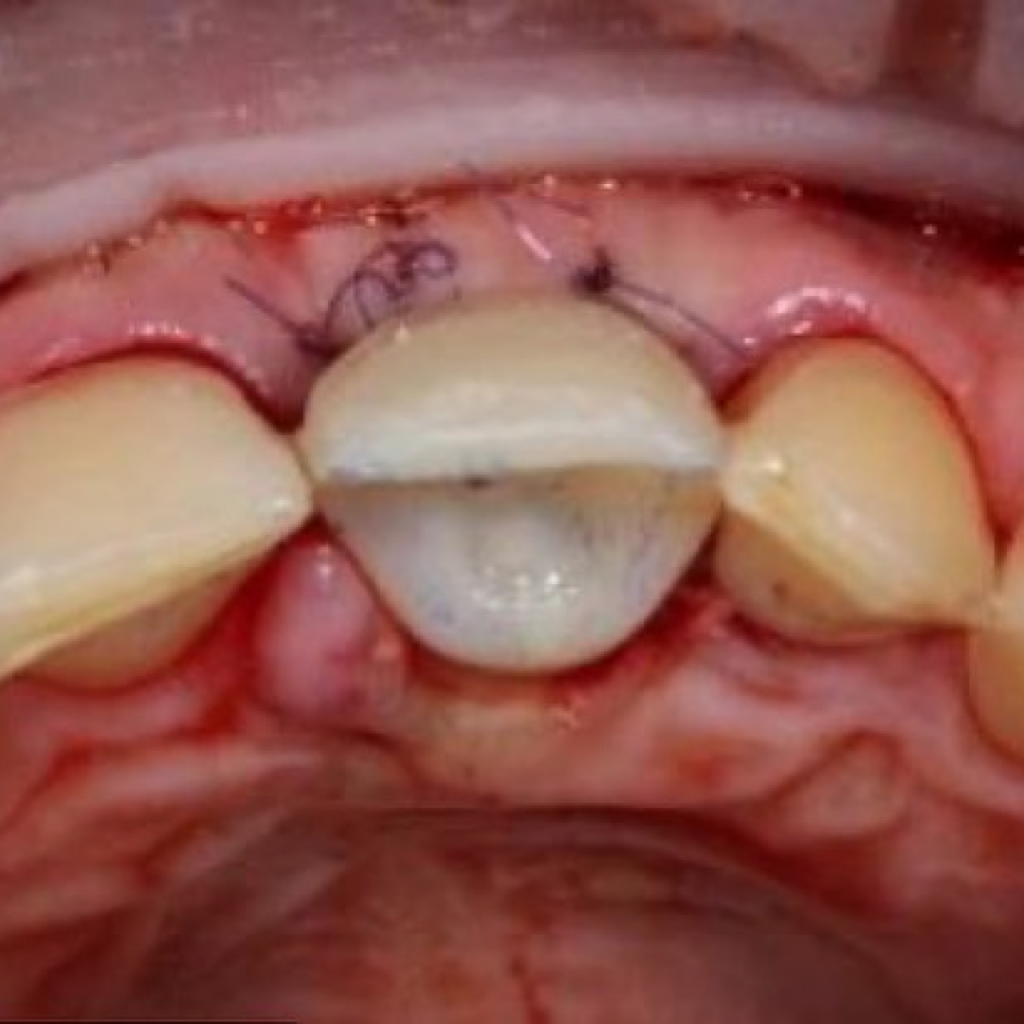

- Лечение: проведена дентальная имплантация AnyRidge в области зуба 2.1 с пластикой десны, а также установлена временная коронка.